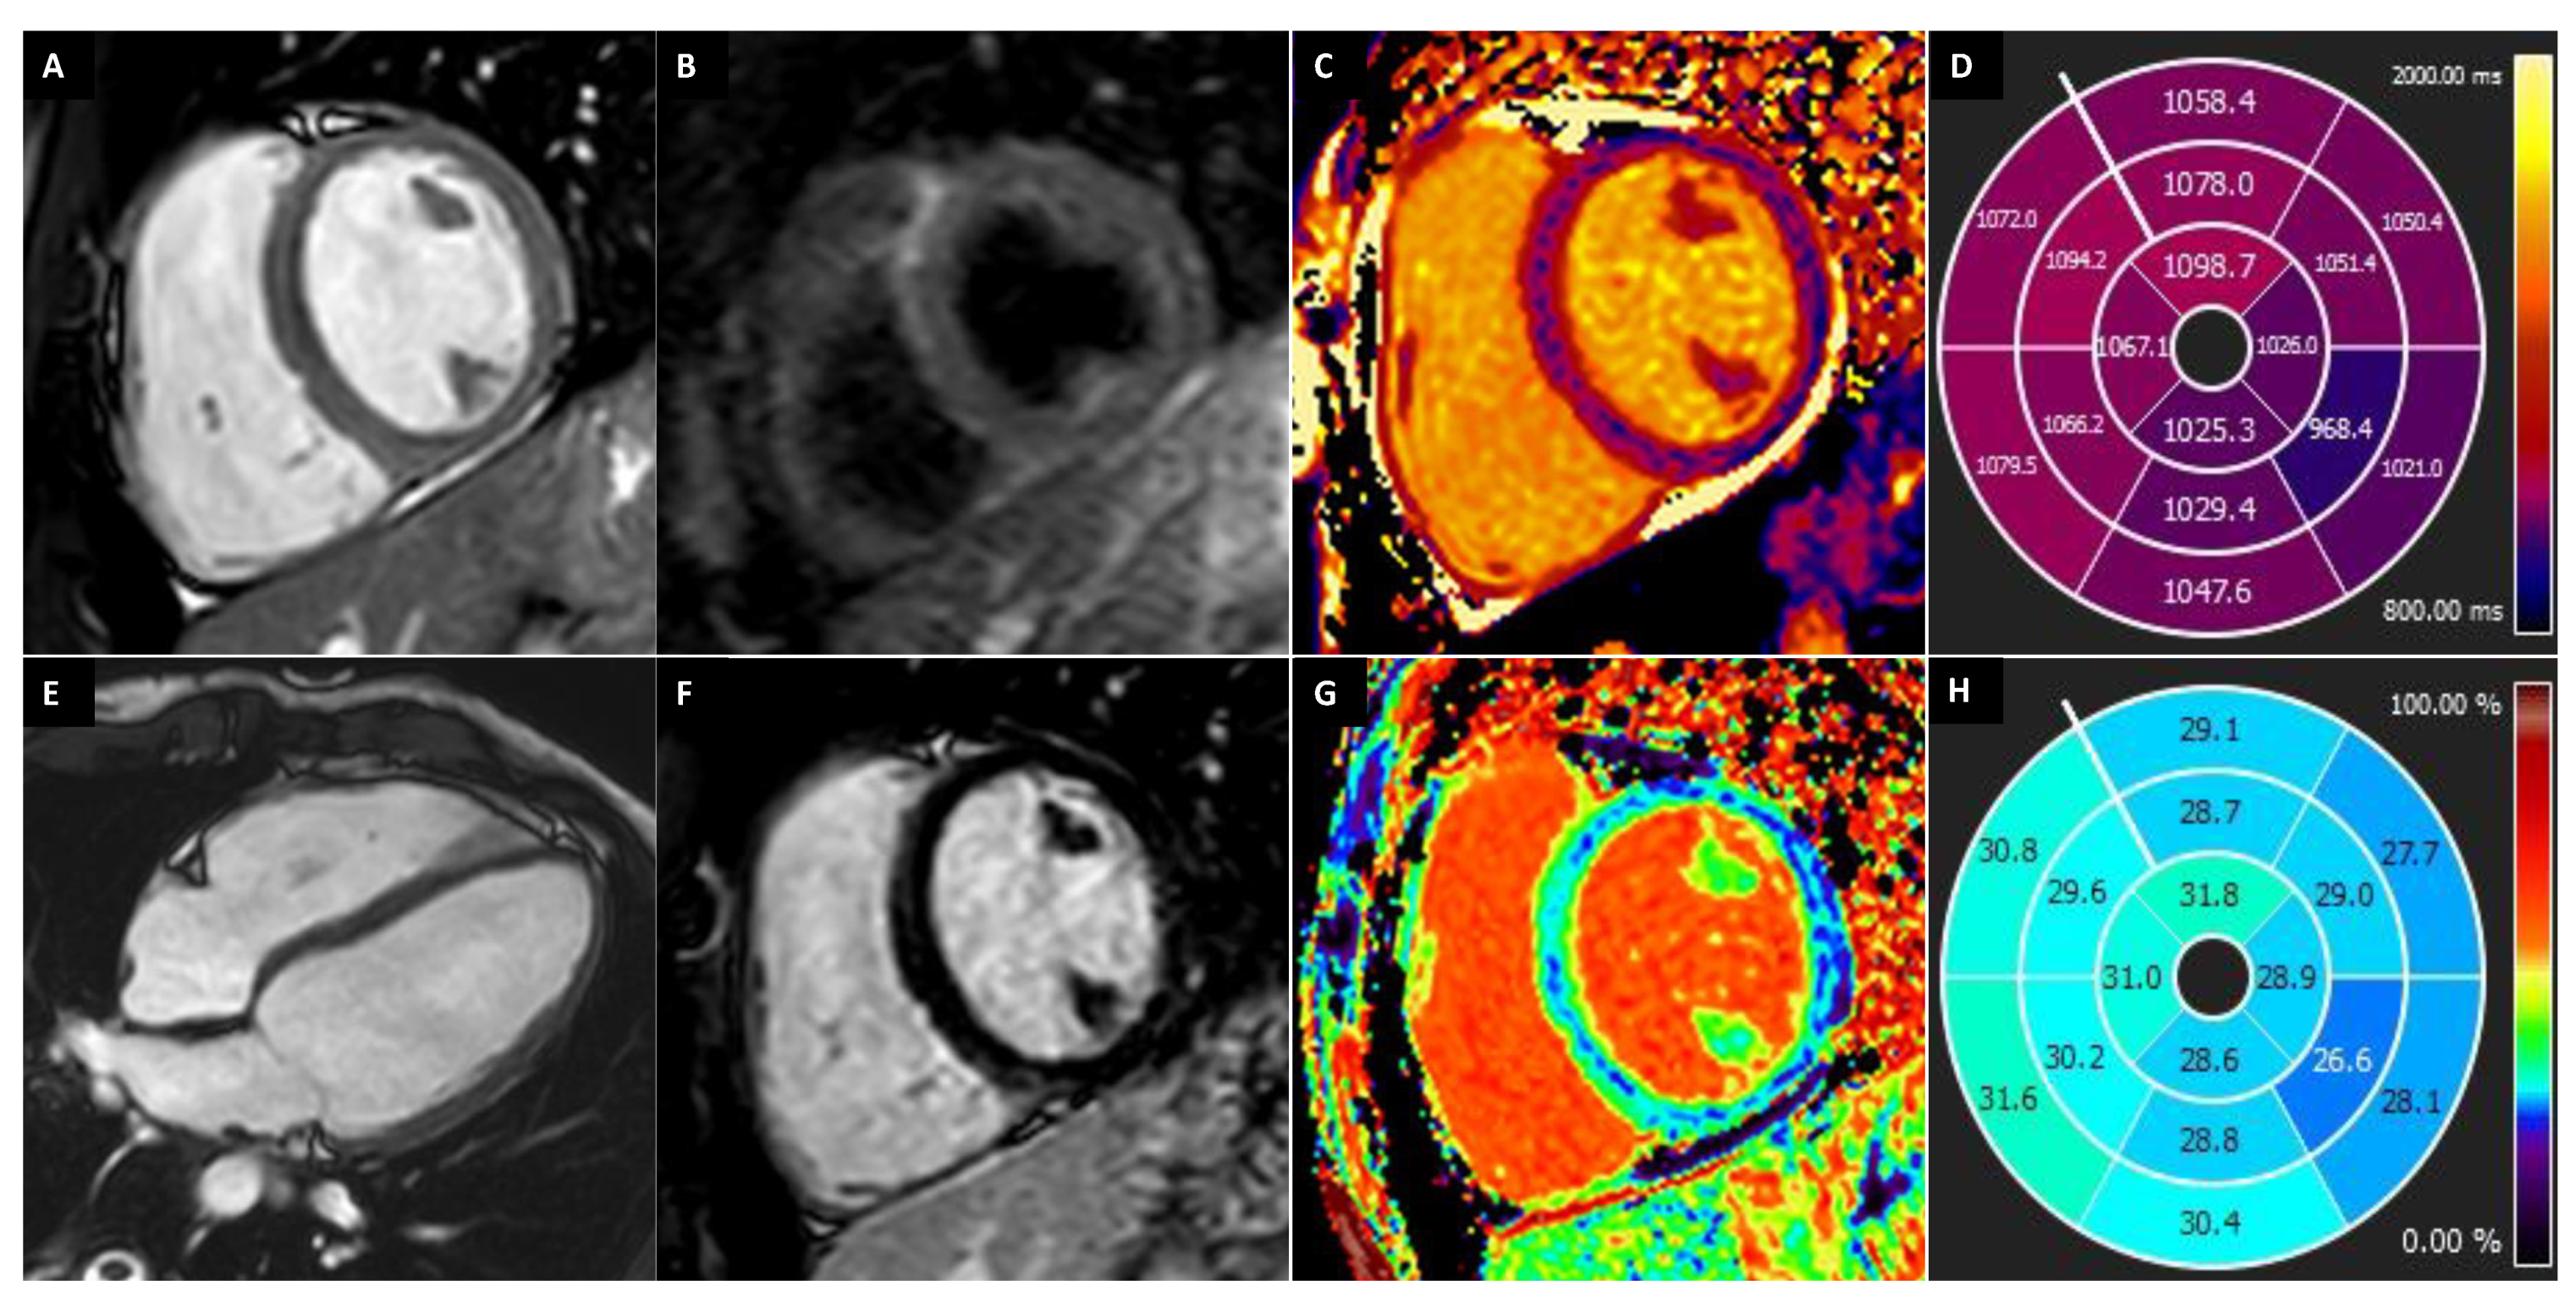

| AH | HCM | DCM | LVNC Cardiomyopathy | ARVD | LDAC | IC | |

|---|---|---|---|---|---|---|---|

| Morphological evaluation | |||||||

| Wall thickness | <15 mm; Symmetric | >15 mm; Asymmetric | - | - | - | - | Mild increased |

| Volume | Increased (LV-RV) | - | Increased (LV-RV) | Increased (LV) | Increased (RV) | Mild increased (LV) | Atrial dilation |

| Trabeculation | Increased | Increased | Increased | NC/C > 2.3 in two cardiac segments | - | - | - |

| Functional evaluation | Normal systolic and diastolic function | Diastolic dysfunction | Systolic dysfunction | LV systolic dysfunction | RV systolic dysfunction | Mild LV systolic dysfunction | Diastolic dys-function |

| Strains and strain rate | Normal | - | - | Reduced | Reduced | - | Reduced |

| Mapping | Reduced (T1-T2) | Increased (T1) | Increased (T1-T2) | Increased (T1) | - | - | Increased (T1) |

| ECV | Reduced | Increased | Increased | - | - | - | Increased |

| LGE/LIE | |||||||

| Type | Linear | Patchy or massive | Linear | Linear | Linear | Linear | Linear or parchy |

| Layer | Mesocardial | Mesocardial | Mesocardial | Mesocardial | Subepicardial Mesocardial | Subepicardial | Subendocardial Mesocardial |

| Site | Interventricular juctions | Hypertrophic area; interventricular junctions | Septum; infero-lateral LV wall | Variable, not associated with NC area | Anterior RV wall | Infero-lateral LV wall | Circumferential; septum; lateral LV wall |